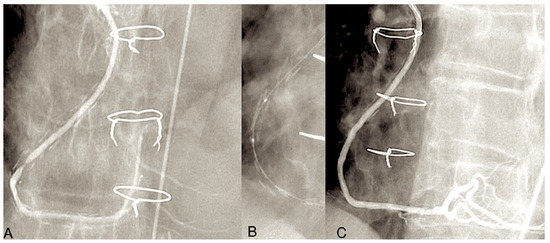

The most common type of angiographic failure observed in radial artery grafts is total obstruction, although a string-like appearance has also been documented. In rare instances, a localised stenosis of the radial artery graft has been identified [151]. Our own experience, spanning two decades, indicates that 6% of RA grafts exhibited stenosis on angiographic controls [151]. In some cases, stenosis was identified at either the proximal or distal anastomosis. In such instances, the potential culprits included a flawed surgical technique or intimal hyperplasia. In more frequent instances, stenosis affected the bodily region of the RA graft, thereby posing challenging pathophysiological concerns. It can often prove problematic to definitively exclude a spasm that is refractory to in situ vasodilators. If identified at an early stage following surgery, the stenosis can be treated with balloon dilation without the need for stenting [151]. If the stenosis is not identified in a timely manner, it is typically of an organic nature. It is possible that some narrowings existed prior to surgery involving the radial artery at the forearm. The development of RA stenosis may be attributable to the presence of an atheromatous plaque that had not been identified at the time of the initial surgical procedure. An additional possibility is that it is associated with fibrosis resulting from arterial trauma caused by inadequate harvesting techniques or prior intravascular procedures. It has been demonstrated that transradial angiography often results in intimal damage and/or medial dissection [152]. In certain instances, the stenosis of the radial artery was identified as a subsequent occurrence, as evidenced by instances where the graft was found to be intact in previous angiograms [151]. It seems plausible to suggest that these vessels may have been the focus of a preceding minor perivascular injury, which subsequently developed into a clinically significant flow-limiting stenosis. It can be reasonably deduced that the occurrence of RA graft stenosis may be prevented by the implementation of a systematic preoperative echo-doppler screening process, coupled with the deliberate preclusion of all calcified RAs and prior interventionally treated conduits. It is possible to safely treat RA graft stenoses by means of PCI and stenting, with the result being durable [151,153]. In regard to percutaneous interventions for venous graft disease, a significant challenge persists due to the high incidence of periprocedural morbidity associated with embolic complications from atherothrombotic detritus (Figure 6) [154].

The illustration depicts the 20-year angiographic control of the radial artery as a secondary conduit on the right coronary artery (RCA), demonstrating the presence of a stenosis at the distal anastomosis. Panels (A–C) illustrate the balloon dilatation of the radial artery (RA) without the use of a stent.